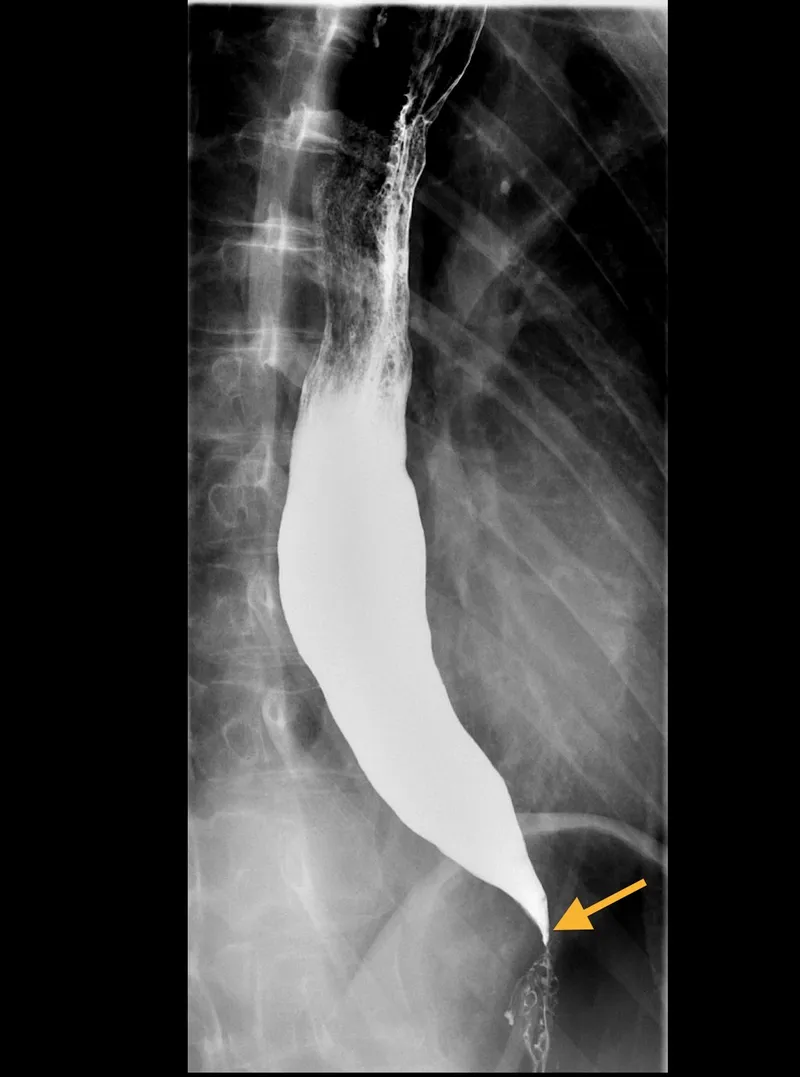

Achalasia: Failure of LES to relax + loss of peristalsis.

- Barium swallow shows a "bird-beak" appearance.

- Achalasia presents with dysphagia to solids and liquids and a "bird's beak" on barium swallow, resulting from the loss of the myenteric plexus.